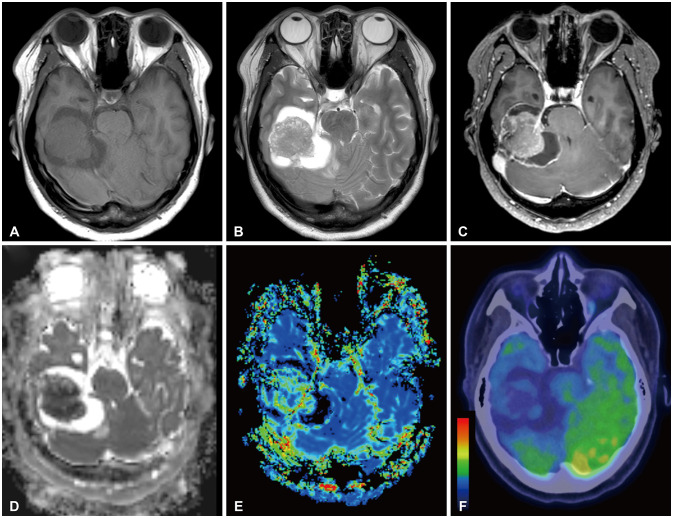

Ewing sarcoma and peripheral primitive neuroectodermal tumor (ES/pPNET) is an undifferentiated malignant tumor that is most prevalent in children and young adults and often radiologically mimics a meningioma. A 38-year-old female patient visited our hospital with complaints of right-sided tinnitus, right hemiparesis, and imbalance. She underwent preoperative imaging and was subsequently diagnosed as having a meningioma on the petrous ridge. After partial resection, EWSR1-FLI1 gene fusion was confirmed, and she was diagnosed with ES/pPNET. The tumor was successfully treated using a multidisciplinary approach of adjuvant chemo- and radiotherapy. This case is noteworthy because it is an extremely rare case of an intracranial ES/pPNET, and it is worth sharing our clinical experience that the tumor was successfully treated through a multidisciplinary therapeutic approach even though complete resection was not achieved.